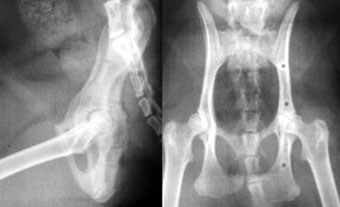

他院からの紹介症例

体重7kg、10か月齢の犬。

腸骨と坐骨の骨折と仙腸関節離断をおこしていました。

腸骨と坐骨はプレート法で整復固定し、仙腸関節離断は創外固定法で整復しました。

写真上段: 手術前

写真下段: 手術後